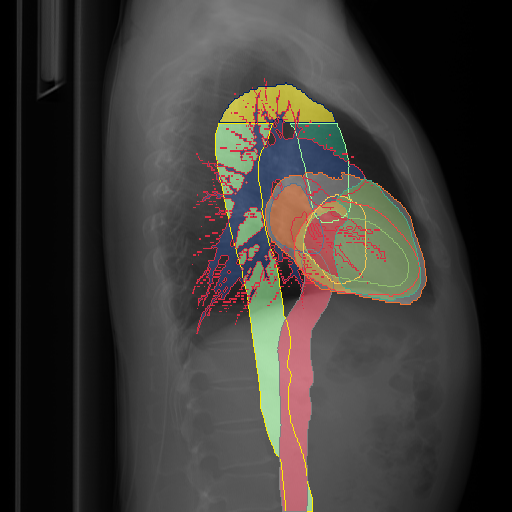

We show qualitative results for frontal projections in Fig. 2. We show a subset of classes belonging to the supercategories lungs, vascular systems, bones, and abdomen/digestive system. The predictions show minor deviations at the boundaries of the individual classes of the respiratory and vasculature system, while some inaccuracies become visible in the abdominal area. The qualitative results for the lateral projections are displayed in Fig. 2. Akin to the frontal view, the predictions show smoother borders but align with the ground truth. Apart from this, the segmentations provide matching insights on the thoracic anatomy with a slight deviation from the ground truth for both frontal and lateral views.

We display qualitative results in Fig. 3. The annotators tend to be content with most annotations. There are edits at the extensions of the esophagus, trachea, and aorta and corrections of the lower ribs. There is little consensus for classes in the abdominal area, such as the stomach, as seen on the right of Fig. 3 . In contrast, the annotators often align for bone classes.